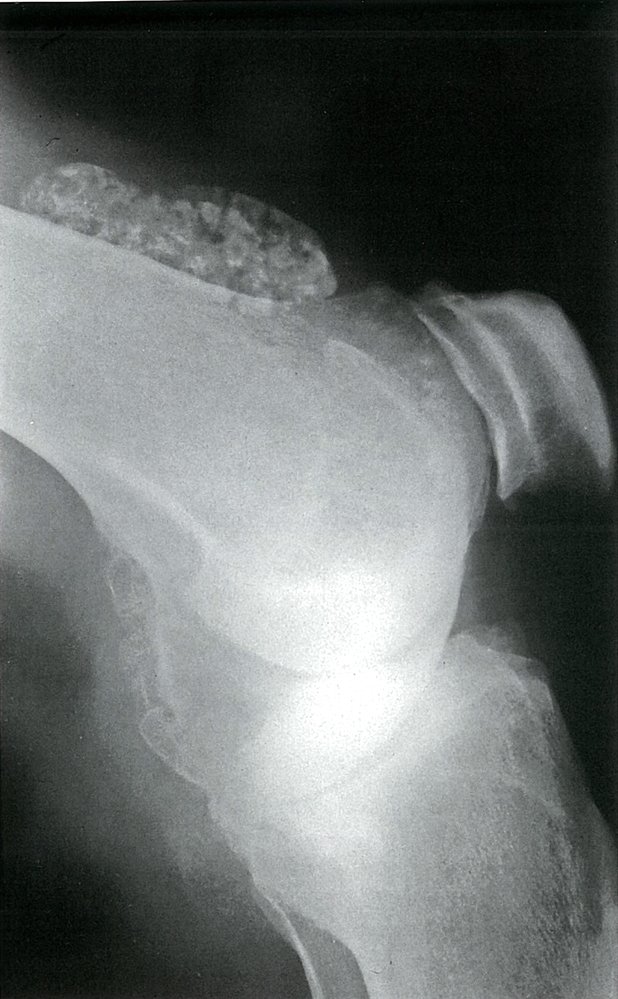

• Description: benign but locally aggressive tumor composed of giant cells that arise from the bone marrow [1]

• Epidemiology: peak incidence between 20 and 40 years

• Clinical features

• Found in the epiphysis or metaphysis of long bones (especially knee region)

• Pathological fractures

• Local pain and swelling

• Limited range of motion

• Diagnostics

• X-ray: multicystic osteolytic lesions (soap-bubble appearance)

• Histopathology

• Mononuclear, RANKL-expressing cells (neoplastic)

• Multinucleated giant cells (are reactive and resemble osteoclasts)

• Treatment: curettage and bone grafting or en-bloc resection to minimize recurrence rate

• Prognosis: risk of malignant degeneration increases with age; may spread to the lungs